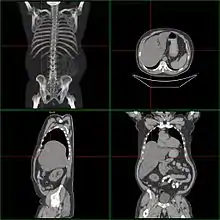

Если размер печени по l. medioclavicularis dextra превышает 12 см или пальпируется левая доля в эпигастральной области, говорят об увеличении печени. Важно исключить опущение печени (например, при хронической обструктивной болезни лёгких или вздутии правого лёгкого) или расположение в правом верхнем квадранте других тканей (увеличенный желчный пузырь, опухоль почки или кишки). Размеры печени лучше определить посредством КТ или УЗИ. Важно оценить контуры и рисунок ткани органа; Увеличение тех или иных участков ткани; «каменистая» консистенция предполагает наличие опухоли; боль при пальпации говорит о воспалении (гепатит) или быстром увеличении размеров органа (недостаточность правого сердца, болезнь Бадда — Киари (Budd-Chiari syndrome), жировая инфильтрация).